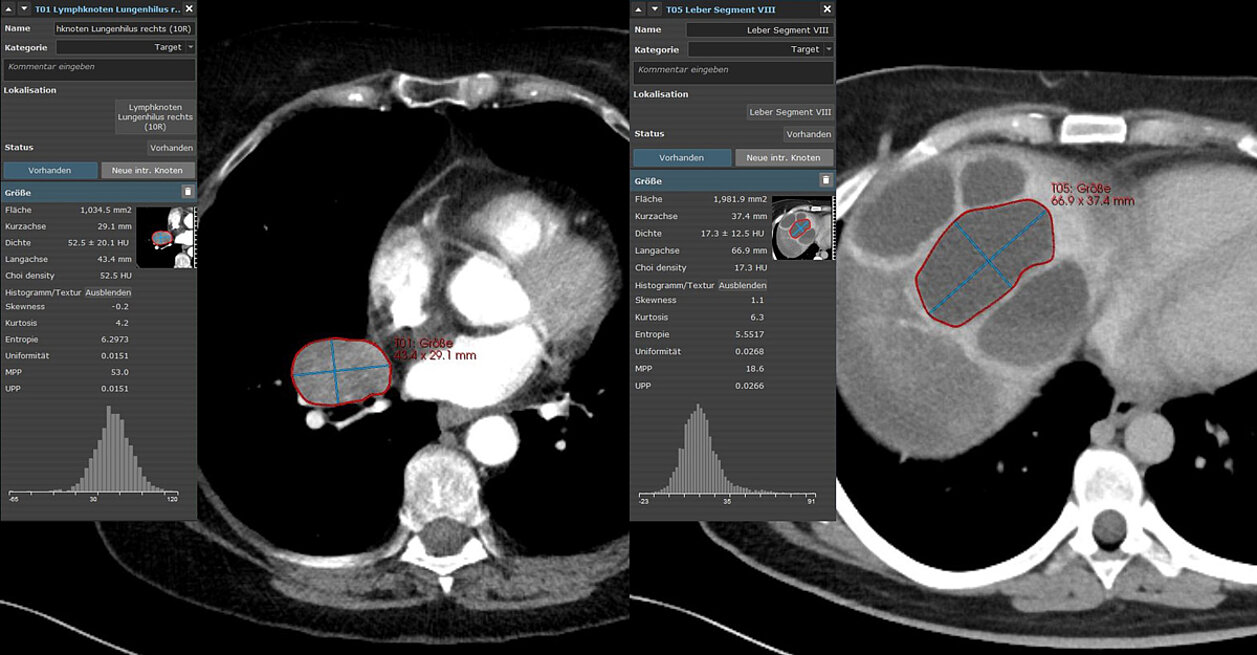

103 Patienten wurden retrospektiv ausgewählt und nach dem Zufallsprinzip der Trainings- (n=69) und Validierungskohorte (n=34) zugeordnet. Klinische und bildgebende Biomarker sowie CT-Texturmerkmale wurden von der größten Target-Läsion (RECIST 1.1) zu Beginn der Studie extrahiert:

- CT-Imaging-Biomarker (Tumorlast und Choi-Dichte) und

- CT-Texturparameter (Entropie, Kurtosis, Skewness, Uniformität, Mean of positive Pixels (MPP) und Uniformity of positive Pixel Distribution (UPP))

mint Lesion™ wurde zur Extraktion der CT-Biomarker und der flächenbezogenen Texturparameter erster Ordnung sowie zur Beurteilung des Behandlungsansprechens gemäß RECIST 1.1 eingesetzt.